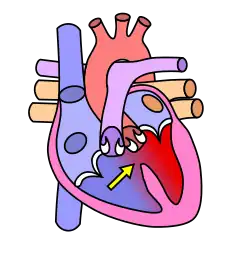

Cardiovascular System

The cardiovascular system, in addition to needing to maintain itself within certain levels, plays a role in maintenance of other body systems by transporting hormones (heart secretes Atrial Natriuretic Peptide and Brain Natriuretic Peptide, or ANP and BNP, respectively) and nutrients (oxygen, EPO to bones, etc.), taking away waste products, and providing all living body cells with a fresh supply of oxygen and removing carbon dioxide. Homeostasis is disturbed if the cardiovascular or lymphatic systems are not functioning correctly. Our skin, bones, muscles, lungs, digestive tract, and nervous, endocrine, lymphatic, urinary and reproductive systems use the cardiovascular system as its "road" or "highway" as far as distribution of things such as nutrients, oxygen, waste products, hormones, drugs, etc. There are many risk factors for an unhealthy cardiovascular system. Some diseases associated are typically labeled "uncontrollable" or "controllable." The main uncontrollable risk factors are age, gender, and a family history of heart disease, especially at an early age.

The cardiovascular system also contains sensors to monitor blood pressure, called baroreceptors, that work by detecting how stretched a blood vessel is. This information is relayed to the Medulla Oblongata in the brain where action is taken to raise or lower blood pressure via the autonomic nervous system.